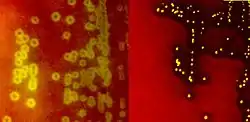

Species of Streptococcus are classified based on their hemolytic properties.[10] Alpha-hemolytic species cause oxidization of iron in hemoglobin molecules within red blood cells, giving it a greenish color on blood agar. Beta-hemolytic species cause complete rupture of red blood cells. On blood agar, this appears as wide areas clear of blood cells surrounding bacterial colonies. Gamma-hemolytic species cause no hemolysis.[11]

When alpha-hemolysis (α-hemolysis) is present, the agar under the colony will appear dark and greenish due to the conversion of hemoglobin to green biliverdin. Streptococcus pneumoniae and a group of oral streptococci (Streptococcus viridans or viridans streptococci) display alpha-hemolysis. Alpha-hemolysis is also termed incomplete hemolysis or partial hemolysis because the cell membranes of the red blood cells are left intact. This is also sometimes called green hemolysis because of the color change in the agar.

Beta-hemolysis (β-hemolysis), sometimes called complete hemolysis, is a complete lysis of red cells in the media around and under the colonies: the area appears lightened (yellow) and transparent. Streptolysin, an exotoxin, is the enzyme produced by the bacteria which causes the complete lysis of red blood cells. There are two types of streptolysin: Streptolysin O (SLO) and streptolysin S (SLS). Streptolysin O is an oxygen-sensitive cytotoxin, secreted by most group A Streptococcus (GAS), and interacts with cholesterol in the membrane of eukaryotic cells (mainly red and white blood cells, macrophages, and platelets), and usually results in beta-hemolysis under the surface of blood agar. Streptolysin S is an oxygen-stable cytotoxin also produced by most GAS strains which results in clearing on the surface of blood agar. SLS affects immune cells, including polymorphonuclear leukocytes and lymphocytes, and is thought to prevent the host immune system from clearing infection. Streptococcus pyogenes, or GAS, displays beta hemolysis.

Alpha-hemolytic S. viridans (right) and beta-hemolytic S. pyogenes (left) streptococci growing on blood agar